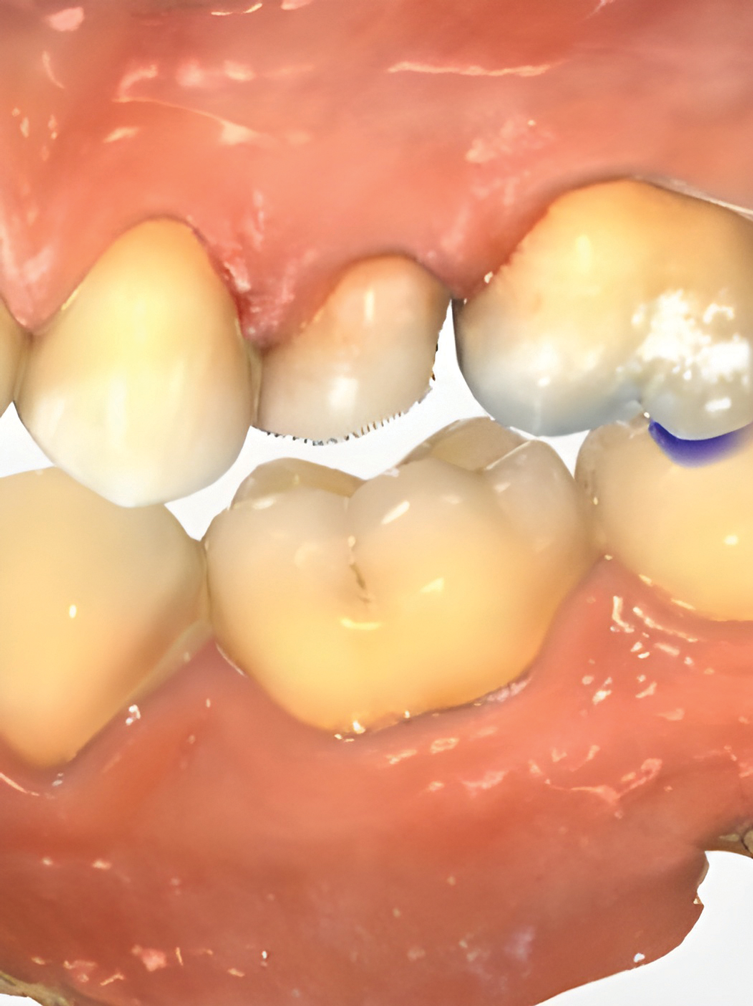

IOSs have found extensive applications across various dental specialties.1 In restorative dentistry, they are primarily used for fabricating dental restorations through CAD/CAM workflows, which remains by far their most widespread use (Figure 1 through Figure 5).2 The accuracy of IOSs enables dental professionals to produce restorations with precision that is on par with conventional methods.3 In addition to restorative dentistry, IOSs are being utilized for various applications in prosthodontics, orthodontics, forensic dentistry, and oral and maxillofacial surgery.

Fig 1 through Fig 5. Single-visit restoration of a maxillary second premolar following root canal treatment. Fig 1: Morphology-guided overlay preparation. Fig 2: IOS bite registration via imaging of buccal tooth surfaces. Fig 3: Preparation margin defined following IOS impression. Fig 4: Overlay design on the IOS platform, integrating adjacent tooth anatomy. Fig 5: Bonded overlay fabricated from CAD/CAM resin-based composite. Fig 6 through Fig 9. Digital workflow for guided endodontics using a digital twin, created by registering an IOI with CBCT data.

Figure 2